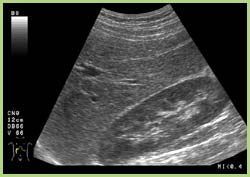

Die Sonographie ermöglicht die Untersuchung

Hierbei können Veränderungen der Organe harmloser Art (z.B. Cysten) aber auch gefährlicher Art (z.B. Bauchaortenaneurysma) festgestellt werden. Ebenfalls kann hierbei sehr sicher beurteilt werden, ob zum Beispiel Gallensteine oder Nierensteine vorhanden sind.

Es handelt sich um ein harmloses und für den Patienten nicht belastendes Untersuchungsverfahren.